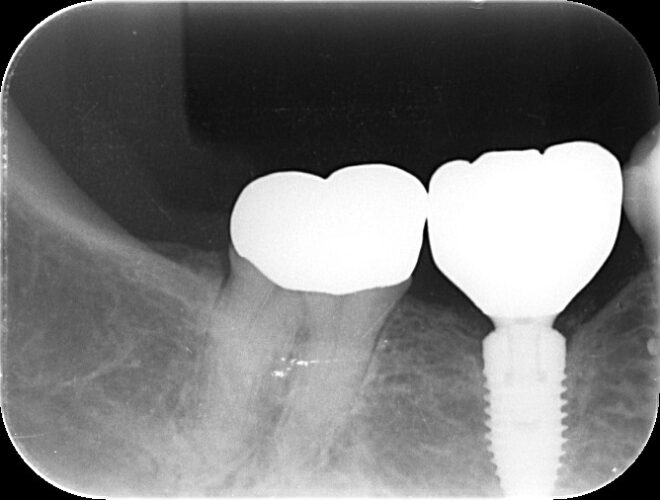

こちらは先月撮ったレントゲン写真になります

インプラントを埋入してから4年経過していますが、骨の量が減ることもなく安定しています✨